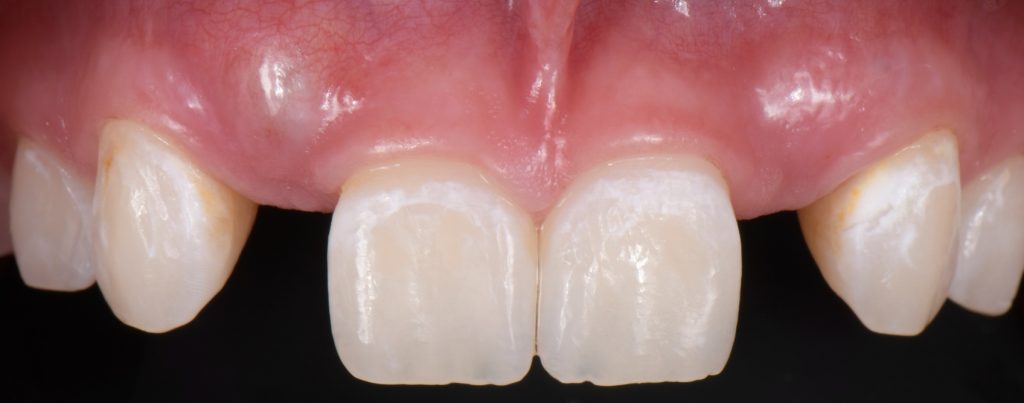

Solution #3: Cantilever Bridge

A fundamental principle in contemporary therapy is to conserve tooth structure by being as minimally invasive as possible. Today, doing a full-coverage restoration on intact natural teeth is extremely difficult to justify, but there are specific conditions where a cantilever bridge can be considered a choice solution.

In this case, a 16-year-old female (Figs. 13-23) presented with congenitally missing lateral incisors with significantly undersized canines that were out of occlusion. Both these specific features meant that from a functional and esthetic standpoint (tooth position and size), the canines required additional contour to attain a favorable occlusal contact and a more dominant contour, characteristic of a maxillary canine.

So, I needed to make sure that there was enough space for the restorative material. A purely additive wax-up was required to attain a mockup, verifying that the proposed contours were esthetically pleasing. This can be obtained either by an analogic approach (Fig. 15) or a digital approach (Fig. 16).

Incisally, there was no reduction required, the reduction was minimal, and from a cervical perspective, a 0.5 mm finish line was prepared (Fig. 17). This allowed our team to do a fundamentally additive design.

It is important here to emphasize that even if the age and preference of the patient allowed us to plan for an implant-supported restoration to replace the lateral incisors, the need to enhance the contours of the canines would still be required to provide a functional and esthetically pleasing result.

The undersized canines were out of function, removing all protective coverage for the lateral incisors. This provided a unique opportunity and indication for the most conservative scenario of a cantilevered RBFDP.